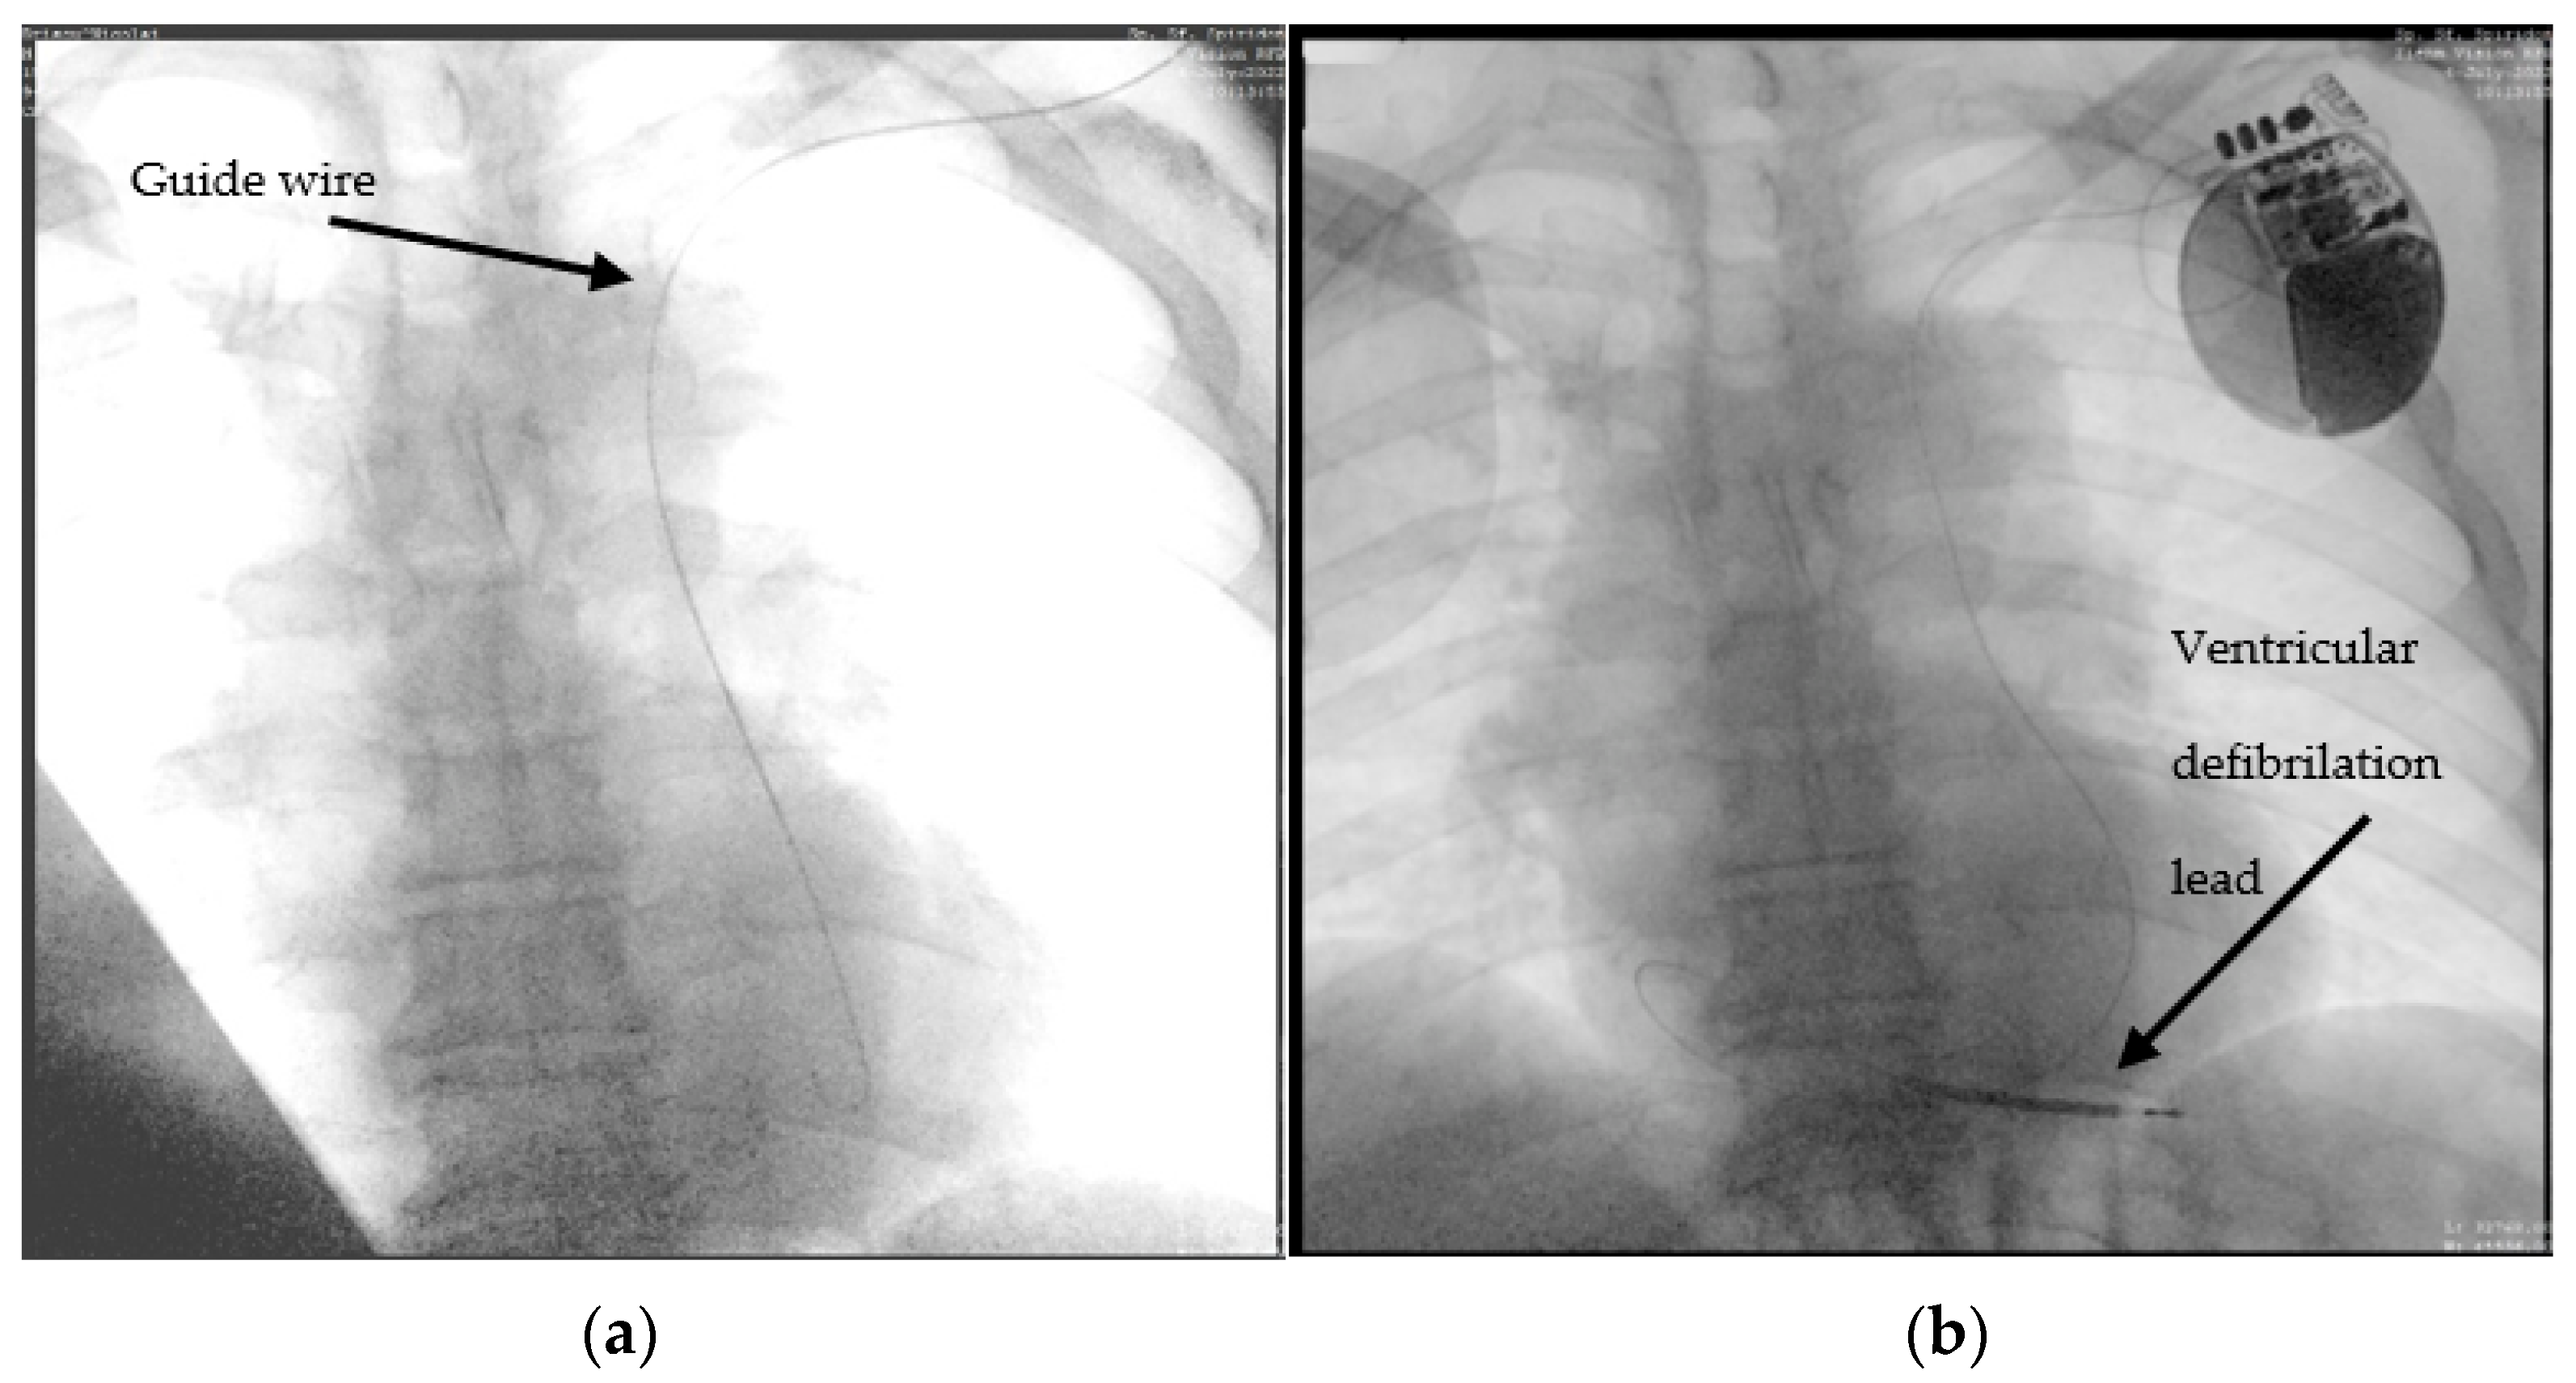

A 63-year-old male patient, with multiple cardiovascular pathologies (an anteroseptal myocardial infarction for which a balloon percutaneous transluminal angioplasty was performed) sent to the emergency unit for the occurrence of fast-paced palpitations, associated with anterior chest pain. The initial electrocardiogram objectified ventricular tachycardia, for which one external electrical shock was delivered (150J) coinciding with the restoration of sinus rhythm. The blood tests revealed a normal hemogram, elevated Nt-proBNP, and positive myocardial cytolysis enzymes. Considering the anamnesis and paraclinical data, a coronary angiography was performed, which excluded the possibility of an acute myocardial infarction. According to current guidelines [7], the next step was the implantation of an ICD. During ICD implantation, puncture of the left subclavian vein, revealed PLSVC, incidentally found during the advancement of the guide wire from the left subclavian vein to the superior vena cava (SVC) (Figure 2a). A venography was performed, which showed no connection between right and left superior vena cava (type IIIb). With some difficulty, we managed to advance with a 9F defibrillation lead (Boston Scientific RELIANCE 4-FRONT™, length 64 cm) through the coronary sinus in the right atrium, and then using a J-shaped stylet to the right ventricle. Finally, we placed the lead at the right ventricular apex, as can be seen in Figure 2b.

Figure 2.

Advance of the ICD ventricular lead through persistent left superior vena cava, coronary sinus, right atrium, and finally, the right ventricle: (a) the guide wire (marked) descending to the left side of the spine; (b) the ventricular lead placed through the left SVC and coronary sinus into the RV.